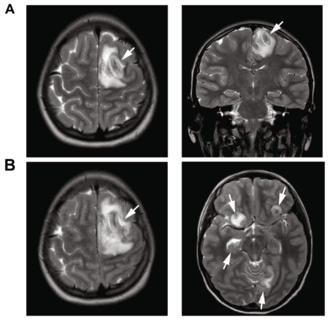

А: T2-взвешенный МРТ показывает разжиженную, некротическую ткань мозга в результате ГАЭ, вызванного Balamuthia mandrillaris

B: T1-взвешенный МРТ показывает расширение и добавление некротических участков через 4 дня